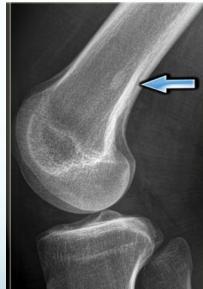

X-rays

- Which bone, and which site in bone?

- Solitary or multiple?

- Bone forming or bone eating?

- Margins: well-defined or ill-defined?

- Calcifications in the lesion?

- Is cortex eroded or destroyed?

- Is there periosteal new bone formation?

- Soft tissue extension?